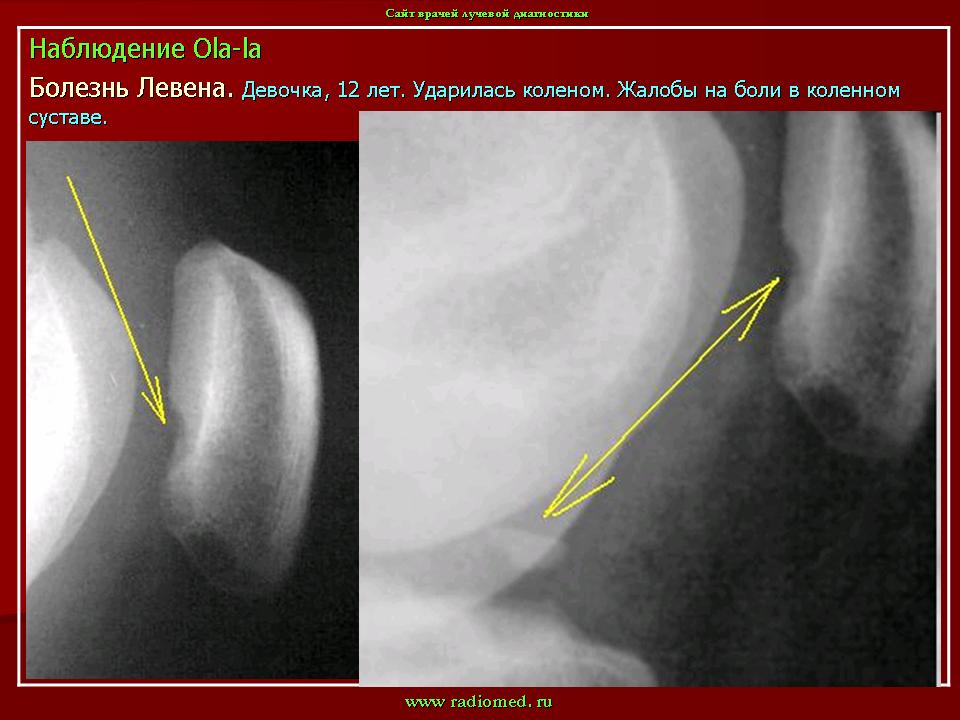

ХОНДРОПАТИЯ НАДКОЛЕННИКА (болезнь Левена). Этиология и патогенез. Чаще всего развивается после мелких повторных травм надколенника (у футболистов, бегунов, баскетболистов и т. д.), значительно реже — после однократной сильной травмы.